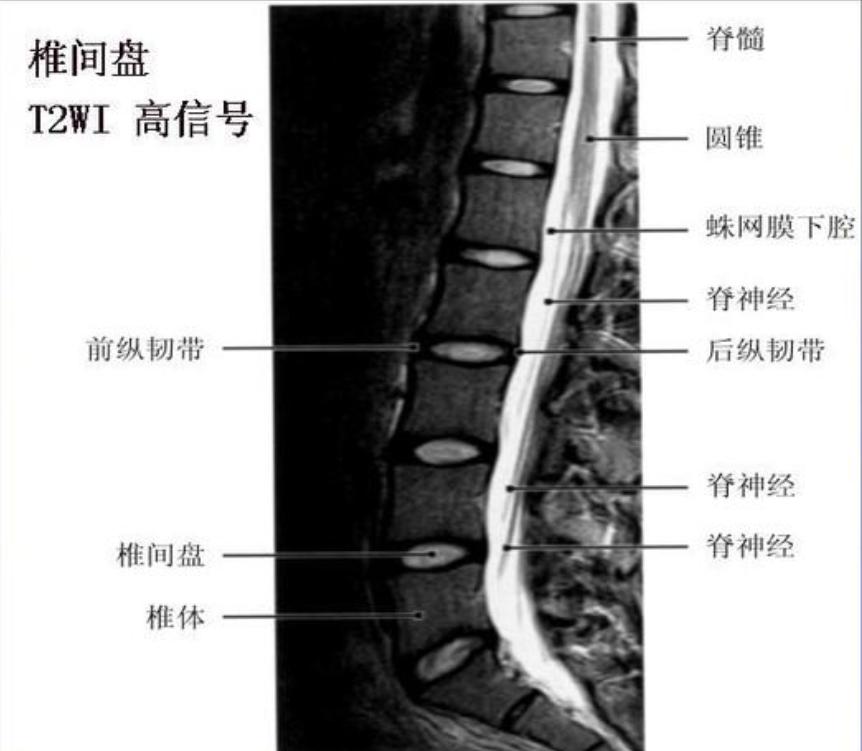

椎管壁的构成椎管是一骨纤维性管道,其前壁由椎体后面、椎间盘后缘和后纵韧带构成,后壁为椎弓板、黄韧带和关节突关节,两侧壁为椎弓根和椎间孔。

发病位置:椎间盘突出是指椎间盘膨出,腰椎间盘受到压力,发生退变,引发后续疼痛。因为颈腰部纤维环前厚后薄,髓核易向后外侧脱出,突入椎管或椎间孔,压迫脊髓或脊神经,称为椎间盘突出症。当膨出不断增大,向后侵占到椎管,就造成了椎管狭窄。

除了椎间盘膨出可以侵占椎管,管壁周围的组织都可能侵占它,从而导致狭窄。比如椎管后壁的黄韧带,关节突关节等,都会因为退变,劳损产生骨质增生或变厚,从而挤压了椎管。